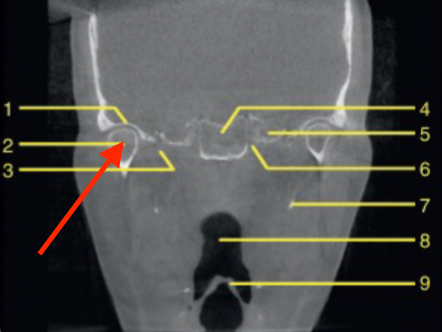

coronal

what plane

posterior of maxillary sinus

where is this slice